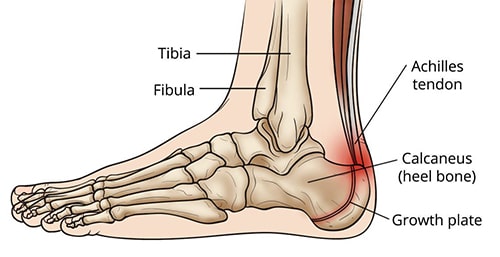

Also known as an osteochondrosis or apophysitis, Sever's disease is an inflammatory condition of the growth plate in the heel bone (calcaneus). Running, jumping, and being active lead to repetitive stress on the growth plate as the foot strikes the ground. This results in inflammation (swelling) in the growth plate, which causes heel pain.

area of pain from Sever's disease

The red shading shows the typical areas of pain from Sever’s disease.